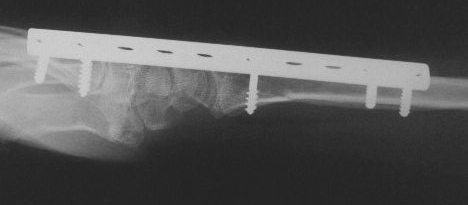

Clinical Example: Distraction plate fixation of distal radius fracture

distal radius fracture

distraction plate